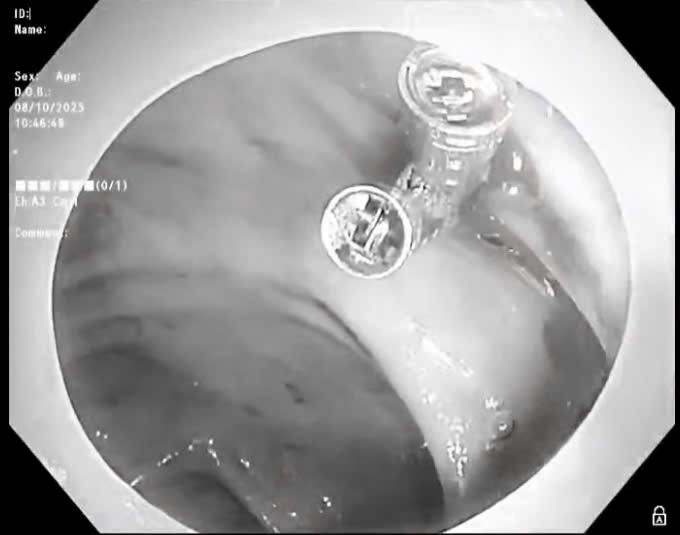

Bệnh viện K tăng cường ứng dụng kỹ thuật EBUS trong chẩn đoán ung thư phổi, hợp tác chiến lược với Bệnh viện Thoraxklinik, Đại học Heidelberg (CHLB Đức)

Thứ Sáu, ngày 17/10/2025 13:56Bệnh viện K tổ chức Hội thảo khoa học “Cập nhật tiến bộ kỹ thuật siêu âm nội soi phế quản (EBUS)”, với sự tham gia giảng dạy trực tiếp của GS.TS.BS.Herth Felix JF, Giám đốc Điều hành và...